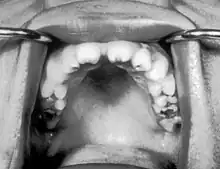

| Notched incisors known as Hutchinson's teeth which are characteristic of congenital syphilis | |

- Blunted upper incisor teeth known as Hutchinson's teeth

A frequently-found group of symptoms is Hutchinson's triad, which consists of Hutchinson's teeth (notched incisors), keratitis and deafness and occurs in 63% of cases.[18]

- Hutchinson's triad, a set of symptoms consisting of deafness, Hutchinson's teeth (centrally notched, widely spaced peg-shaped upper central incisors), and interstitial keratitis (IK), an inflammation of the cornea which can lead to corneal scarring and potential blindness